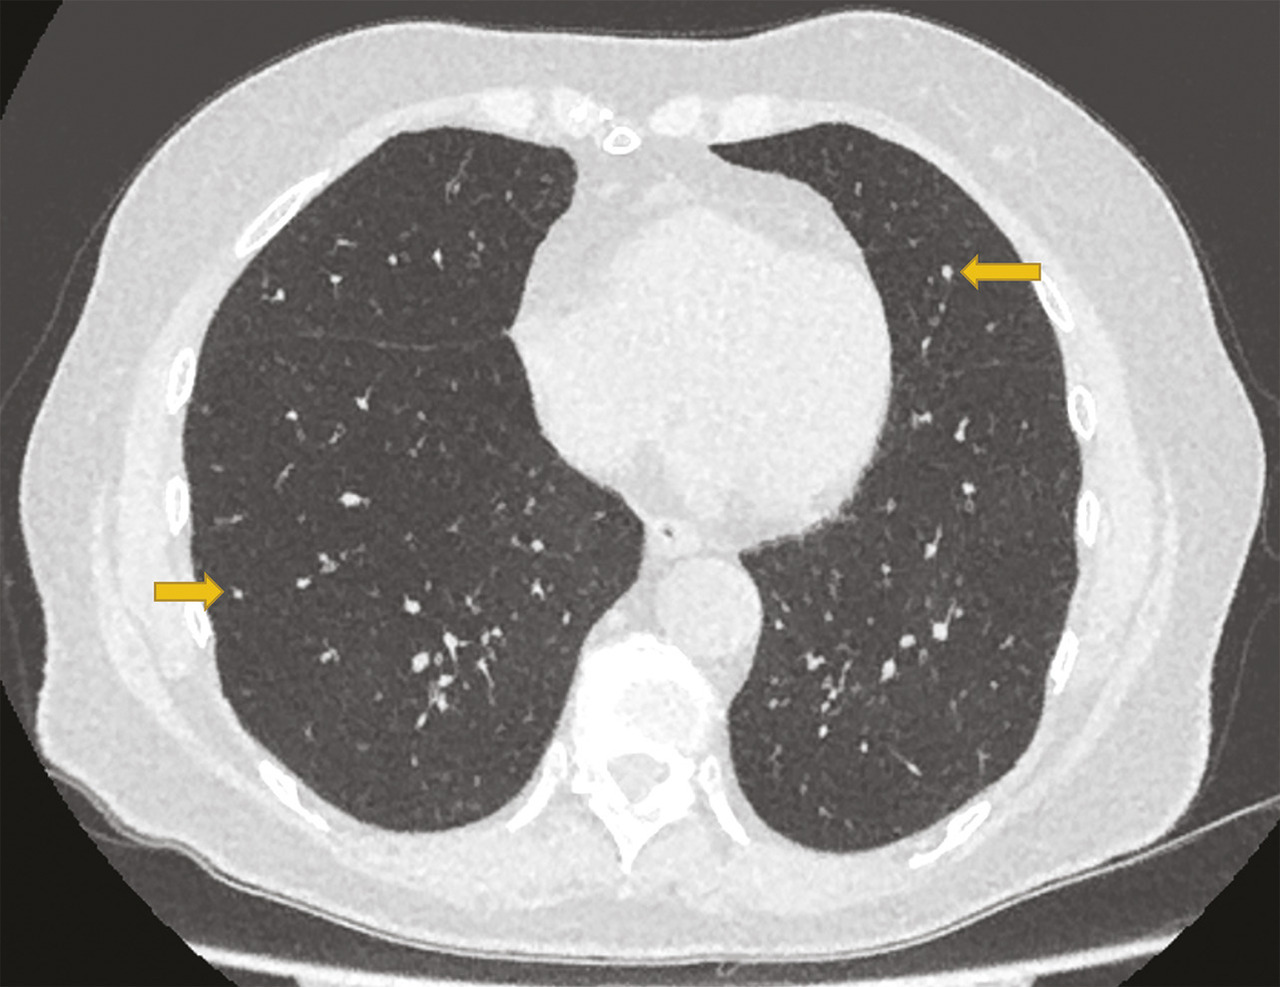

Cette femme de 75 ans consultait pour une toux invalidante, associée à une dyspnée d’effort et des sifflements. Un diagnostic d’asthme tardif avait été fait à l’âge de 47 ans, traité par fluticasone à forte dose (1000 µg/j), salmétérol et montélukast. Malgré le traitement, la toux persistait et la dyspnée s’aggravait progressivement entraînant une limitation importante dans sa vie quotidienne. Les épreuves fonctionnelles respiratoires montraient un trouble ventilatoire obstructif non réversible sévère (VEMS 780 mL soit 36 %, VEMS/CV 40 %) avec une distension thoracique (volume résiduel 198 %). La tomodensitométrie thoracique montrait des micronodules diffus et un aspect en mosaïque évoquant une bronchiolite. Une biopsie pulmonaire chirurgicale était faite ; l’examen anatomopathologique permettait de poser le diagnostic d’hyperplasie neuroendocrine pulmonaire diffuse idiopathique (DIPNECH).

La Dipnech, maladie pulmonaire rare de cause inconnue liée à la ­prolifération des cellules neuro­endocrines de l’épithélium des voies aériennes,1 touche les femmes dans plus de 90 % des cas, souvent d’âge moyen, sans antécédent de tabagisme.1 La toux sèche est fréquente, associée à une dyspnée d’effort, liée au développement progressif de l’obstruction bronchique par une fibrose ­péri­bronchiolaire. Les symptômes évoquent souvent un asthme ou une bronchopneumopathie ­chronique obstructive ; l’errance diagnostique est fréquente.1 Le scanner thoracique est l’examen clé qui montre des ­micronodules diffus et un aspect en mosaïque du parenchyme pulmonaire avec trappage aérien, qui font évoquer une bronchiolite constrictive. Une confirmation histologique par biopsies transbronchiques ou biopsie pulmonaire chirurgicale est indispensable ; elle montre la ­prolifération des cellules neuro­endocrines dans l’épithélium des petites voies aérienne, avec la présence de tumorlets*.1 Le traitement n’est pas codifié L’évolution est le plus souvent lente, mais des formes sévères, nécessitant une transplantation pulmonaire, ont été rapportées. L’utilisation d’un analogue de la somatostatine ou d’un inhibiteur de la voie mTOR (sirolimus) a été rapportée, avec un effet variable sur les symptômes, notamment la toux, et sur la fonction respiratoire.2, 3 Les bronchodilatateurs et les corticoïdes inhalés sont souvent utilisés à titre symptomatique.